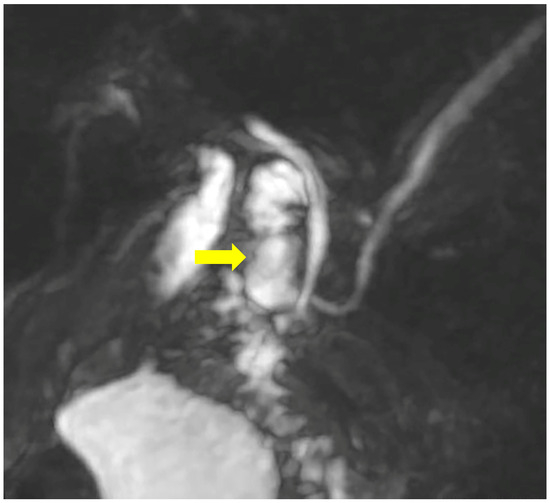

A month later, the patient was readmitted due to upper abdominal pain, a slight elevation of transaminases, alkaline phosphatase, GGT, and amylase. CRP was within a normal range, with unremarkable US/MSCT findings. The magnetic resonance imaging (MRI) demonstrated a duodenal diverticulum adjacent to the papilla, located over the junction of the common bile and pancreatic ducts, which were not dilated (Figure 3 and Figure 4).

Figure 3. MRCP demonstrates the duodenal diverticulum over the junction of the biliary and pancreatic ducts (arrow).